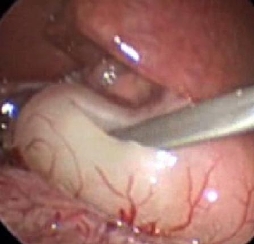

Pyloric stenosis

Muscle-splitting manoeuvre

From the collection of Dr Jeffrey S. Upperman; used with permission